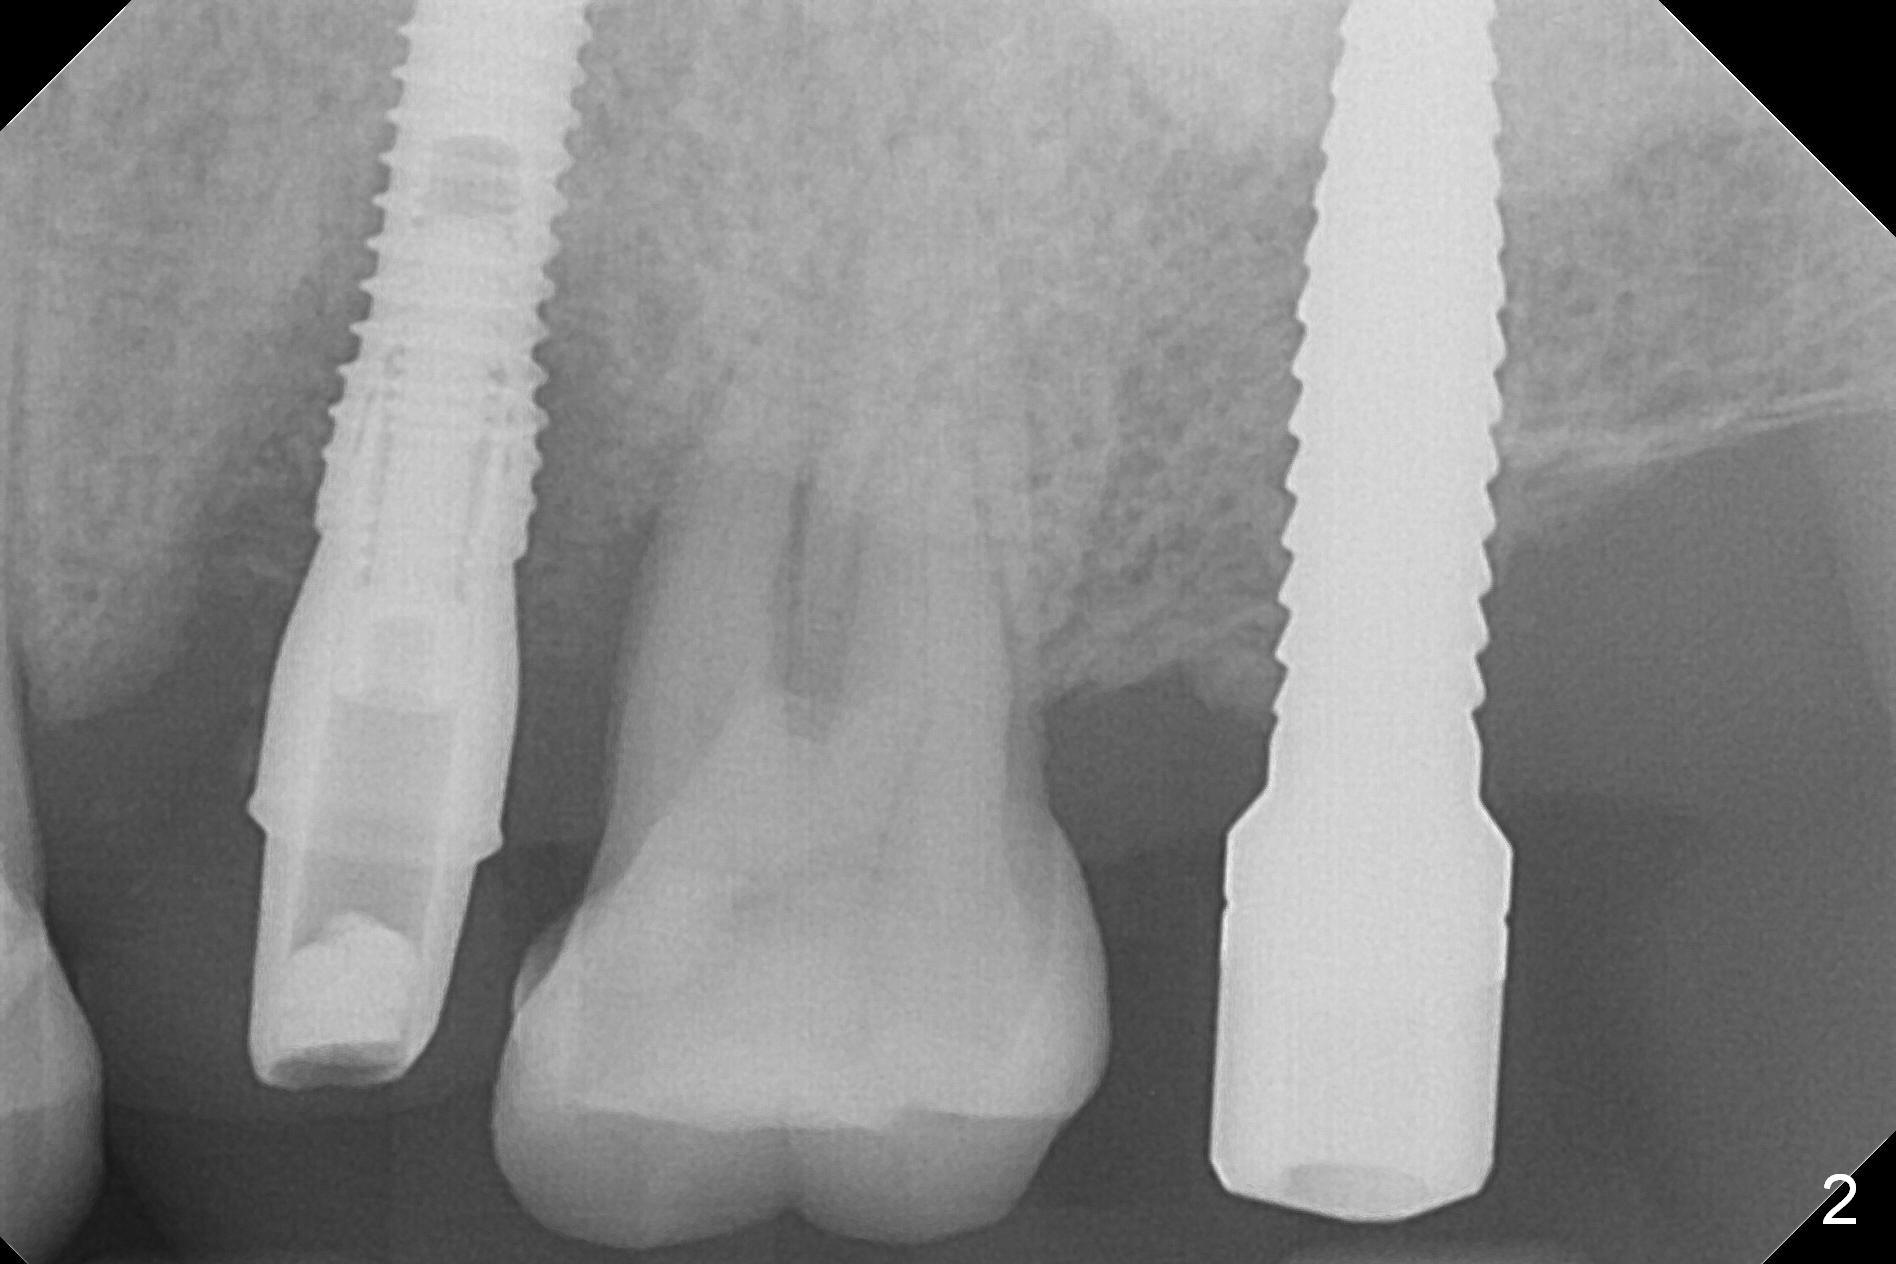

A 1.2 mm initial drill is used to start osteotomy at the site of #15 (Fig.1). After moving the osteotomy distally (with Lindamann bur), the osteotomy is enlarged by DIO Bone Expanders until 2.4/3.7 mm for 18 mm (gingival level) (Fig.2). Following the expander 3.0/4.4 mm, a 5x13 mm UF implant is placed supracrestal (Fig.3,4). After deepening the osteotomy with 3.8 mm drill for 3 mm, the implant is placed deeper by ~ 2 mm (Fig.5 arrow). Since the tooth #18 is supraerupted, a healing abutment (5.5x12(3) mm) is placed (Fig.6: H); the gingiva adapts to the abutment well. Suture is not necessary. The bone remains stable 2 and 4.5 months postop (Fig.7,8). Impression is taken. A crown is delivered nearly 6 months postop (08/07/2017). While there is minimal bone loss at #13 and 15 three years and 4 months post cementation, the tooth #14 and 18 are mobile (Fig.13,14, #13).